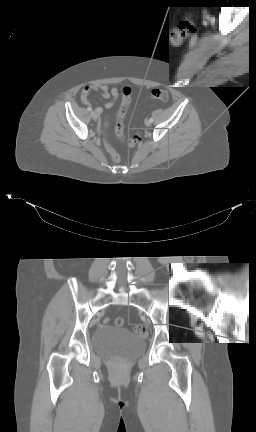

Refer to caption

(a)

(b)

Figure 5: (a) Axial (top) and coronal (bottom) slices of pelvic TV++ reconstruction, HU range=(-400, 400) and (-150, 250) for ROI, (b) LIRE++

This comparison demonstrates that LIRE++ translates well to real CBCT pelvic data. Reconstruction given by LIRE++ is noticeably cleaner than the TV++ reconstruction, scatter artifacts in particular are well-suppressed. Field of view given by LIRE++ is slightly larger compared to TV++. We have measured an improvement in mean HU accuracy, however, due to anatomical differences such comparison can underestimate actual reconstruction quality. TV++, on the other hand, substantially outperforms a classical FDK method with deep-learning scatter precorrection and its calibrated version.

In order to demonstrate that LIRE++ can be scaled to full resolution, we provide sample reconstructions with 1 mm voxel pitch in Figure 5 from the extended version of LIRE++ and compare them to TV++ reconstructions. The reconstructions from LIRE++ are less noisy; however, more finetuning might be needed to completely remove image artifacts.